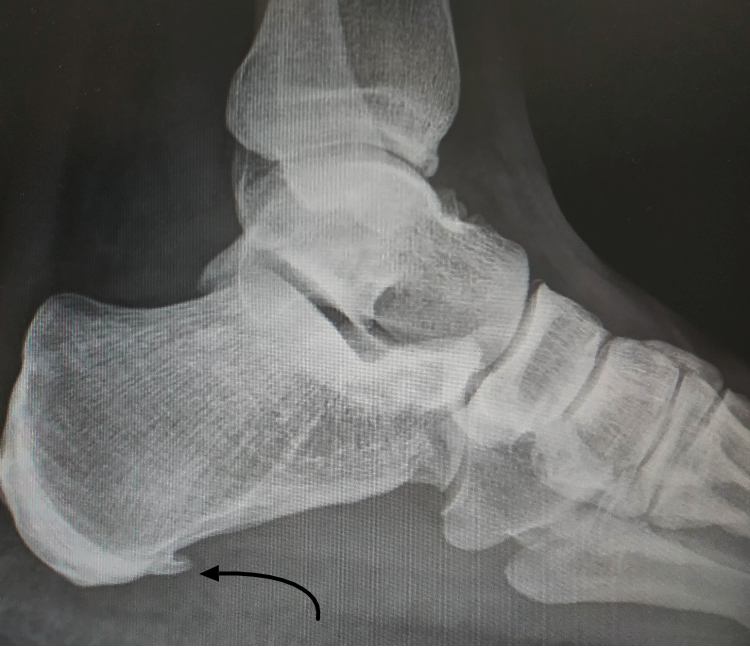

Plantar fascia calcification can occur in the setting of plantar fasciitis 1 or rarely as a sequelae of prior steroid injection 2. Heel spurs on the bottom of the heel are often associated with both plantar fasciitis and plantar bursitis. Plantar fasciitis is a disorder of the insertion of the plantar fascia as it inserts on the calcaneus (heel bone), causing pain in. Plantar fasciitis is by far the most common cause of heel pain. A doctor will usually suspect you have plantar fasciitis based on your symptoms and a physical exam. Plantar fasciitis is usually diagnosed via a medical history, discussion of symptoms and physical examination.

Several findings suggestive of plantar fasciitis can be detected on conventional radiographs. We use ultrasound in our office. It can be quite convincing because theres this extra pointy piece of bone right in the area where your pain is, but the recent research has shown that this is actually not the case. Plantar fasciitis is a clinical diagnosis and is often combined with some form of imaging to validate the diagnosis. Calcific enthesopathy of the achilles tendon is also seen (open arrow) (a).on ultrasound, plantar fasciitis presents with pf.

Once you have a positive plantar fasciitis diagnosis, there are numerous treatment options to. The best way to tell is with an ultrasound image of the bottom of the heel. Plantar fasciitis is a clinical diagnosis and is often combined with some form of imaging to validate the diagnosis. Several findings suggestive of plantar fasciitis can be detected on conventional radiographs. In addition to stress fractures, some mistake gout, achilles tendinitis and other painful conditions for plantar fasciitis, resulting in them suffering unnecessarily while treating the wrong problem.

Ultrasound images clearly show the fluid sac. Plantar fasciitis is a disorder of the insertion of the plantar fascia as it inserts on the calcaneus (heel bone), causing pain in. This will help discover any abnormality, such as a stress fracture or a heel spur. It’s important to understand that heel spurs do not cause pain and you won’t automatically need surgery just because you have a heel spur. Despite this, plain radiography should not be used to make a diagnosis of plantar fasciitis without knowledge of clinical history or physical examination findings.

You will not be able to tell the difference between plantar fasciitis and a heel spur. They can, however, be very valuable in ruling out or confirming a stress fracture. The symptoms for plantar fasciitis and heel spur are the same. Several findings suggestive of plantar fasciitis can be detected on conventional radiographs. The first doctor you will see when you think you have plantar fasciitis is your general practitioner.